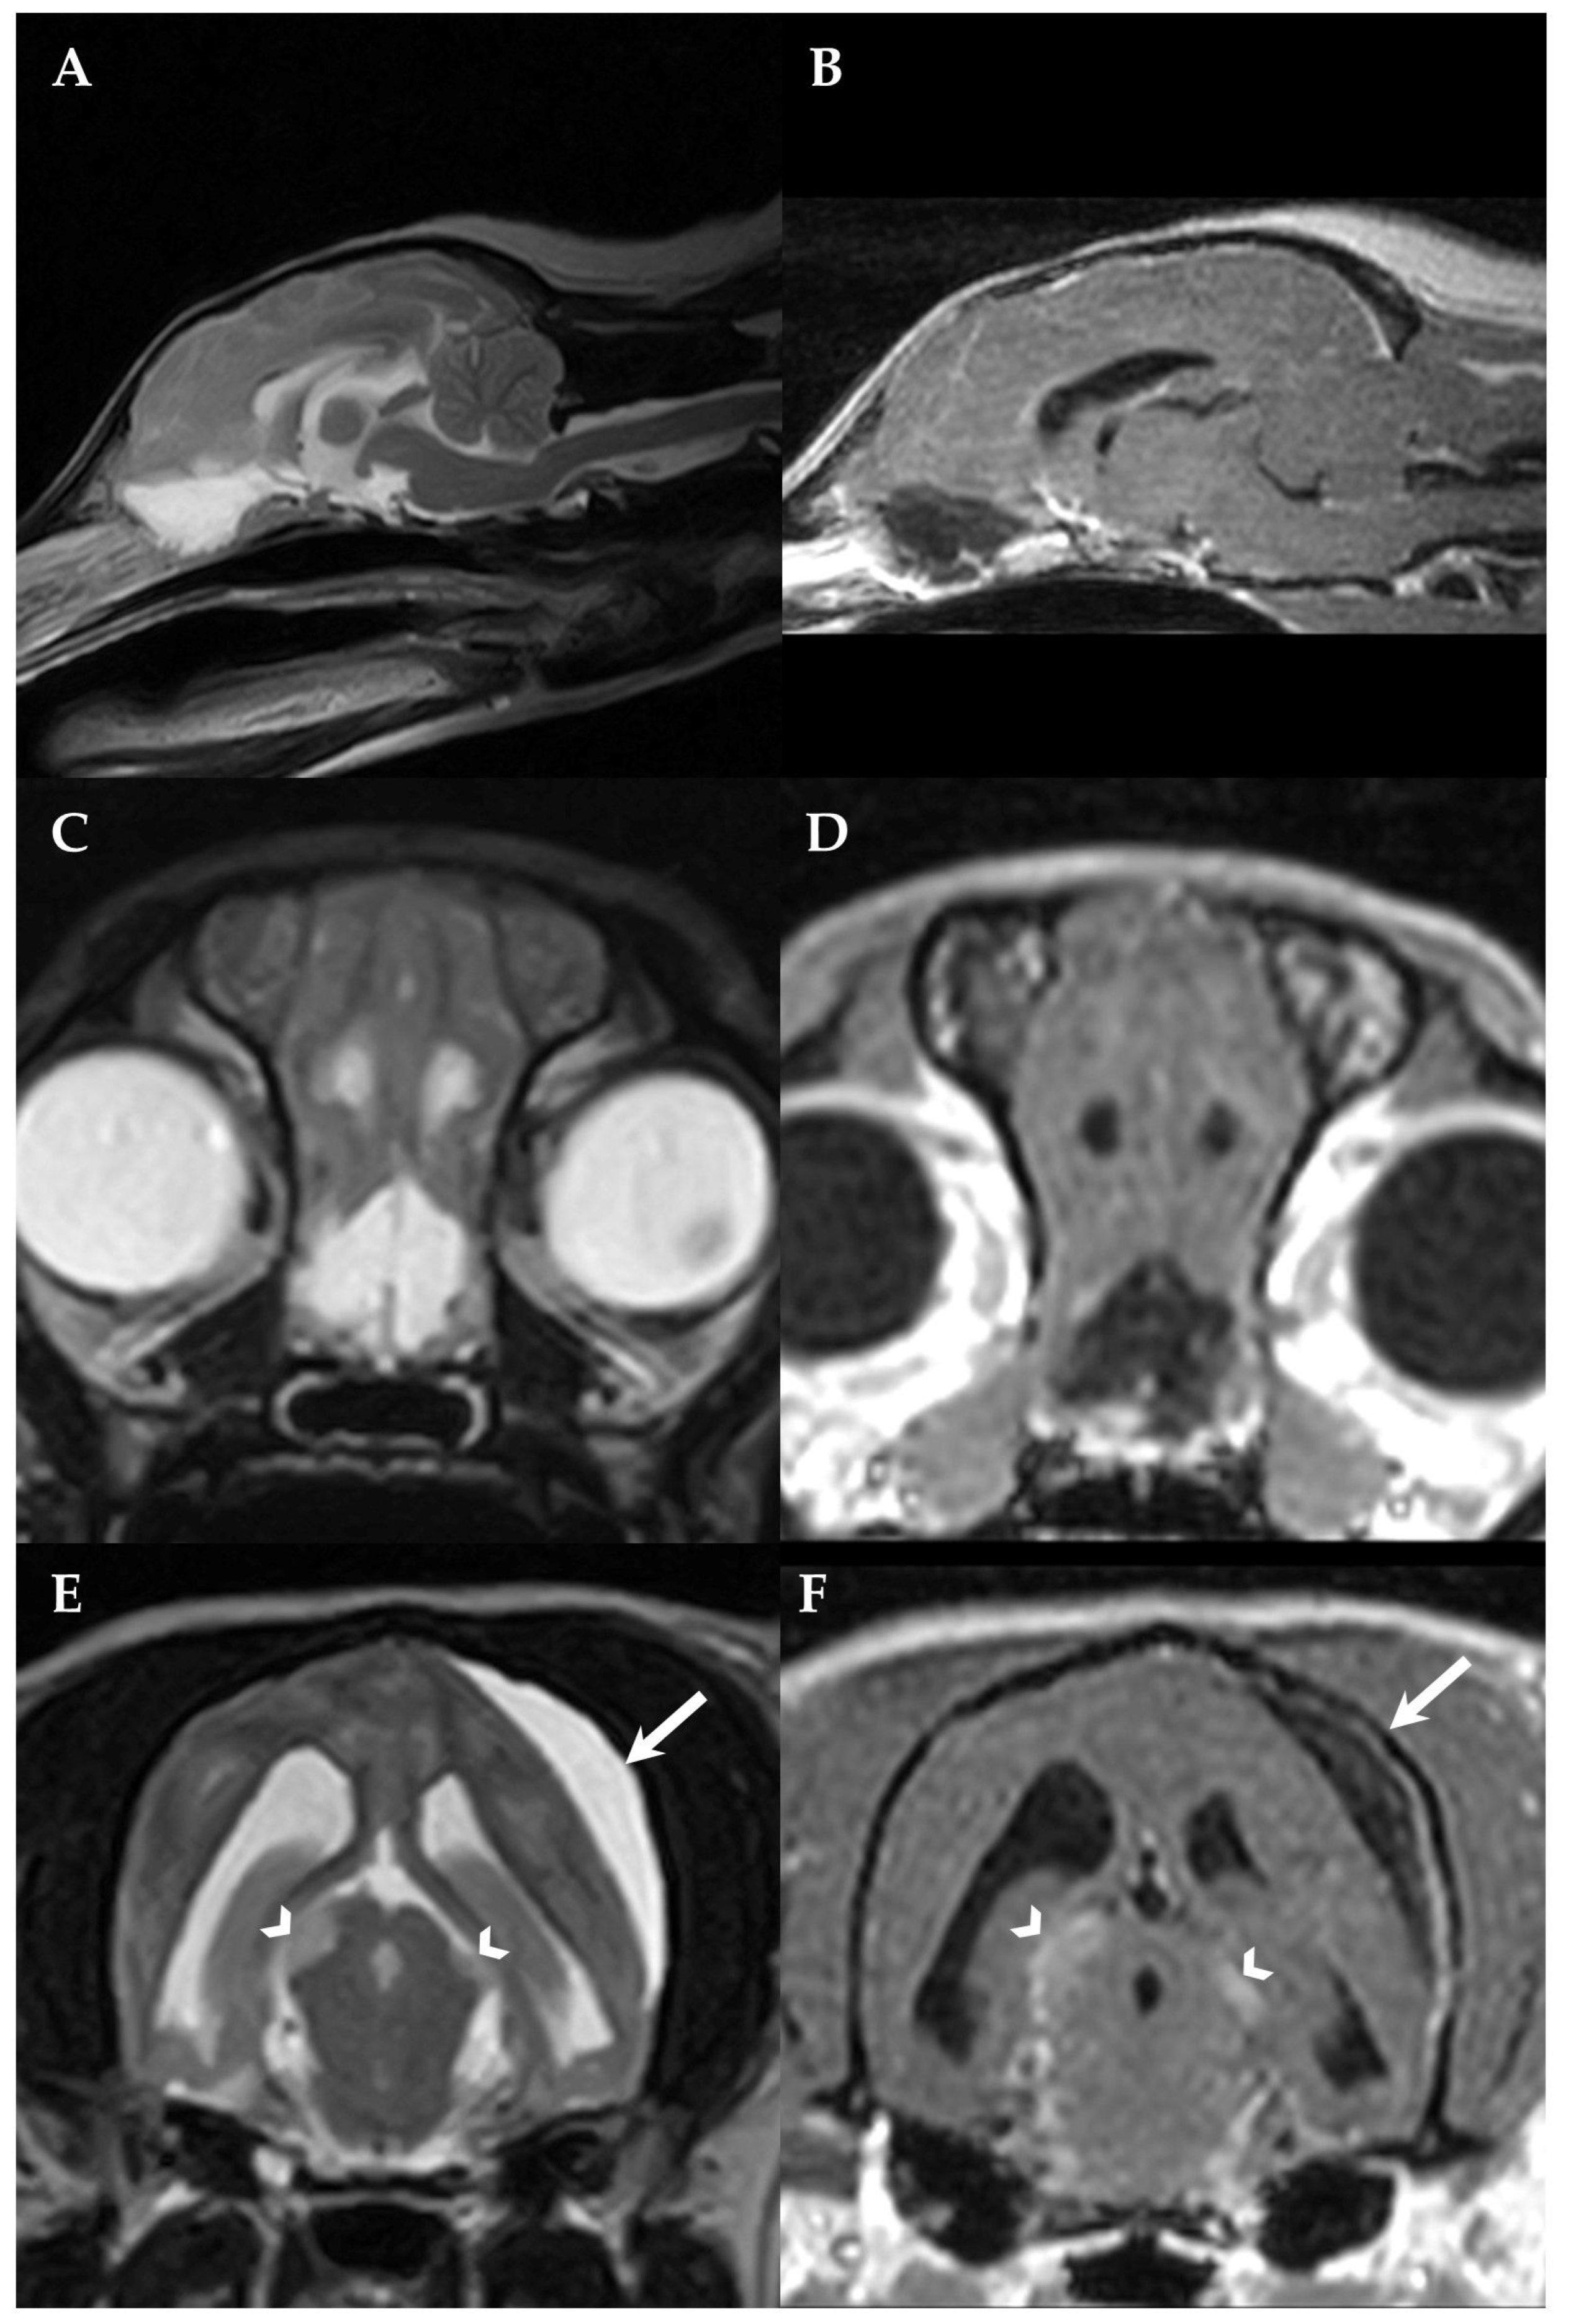

Post-mortem MRI was performed obtaining the same sequences as described for the first MRI excluding post-contrast images and showed a complete resolution of the SFA, a hydrocephalus internus with dilation of olfactory recesses, periventricular FLAIR and T2W hyperintensities consistent with periventricular oedema and a flattening of the interthalamic adhesion as well as an enlargement of the midbrain (Figure 4A) and thalamic lesions that had already been recognized on the first MRI.

Figure 4.

Post-mortem MRI, transverse T2W (A) and frontal brain section, formalin-fixed (B) of the dog’s brain at the level of the midbrain. Post-mortem MRI demonstrated a resolution of the SFA, a moderate hydrocephalus internus and an enlargement of the midbrain lesions (arrowheads, A). On necropsy, the midbrain lesions revealed to be macroscopic tumor foci arising from the subarachnoid space (arrowheads, B). The left side of the patient is on the right side of the image.